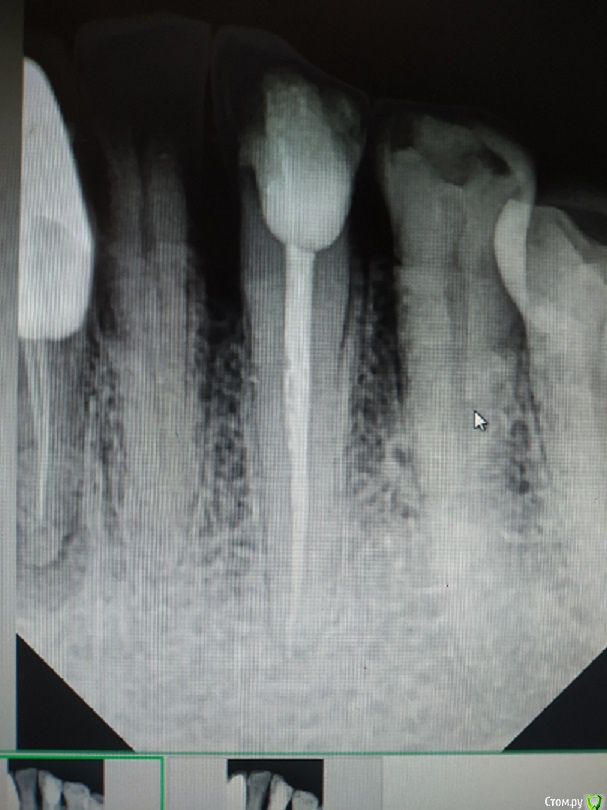

4.6 - острый пульпит. В дистальном 25.04, в медиальных 20.02. Не смог обработать до большего, да и не увидел в этом смысла. В дистальном я силер не выводил, он сам))